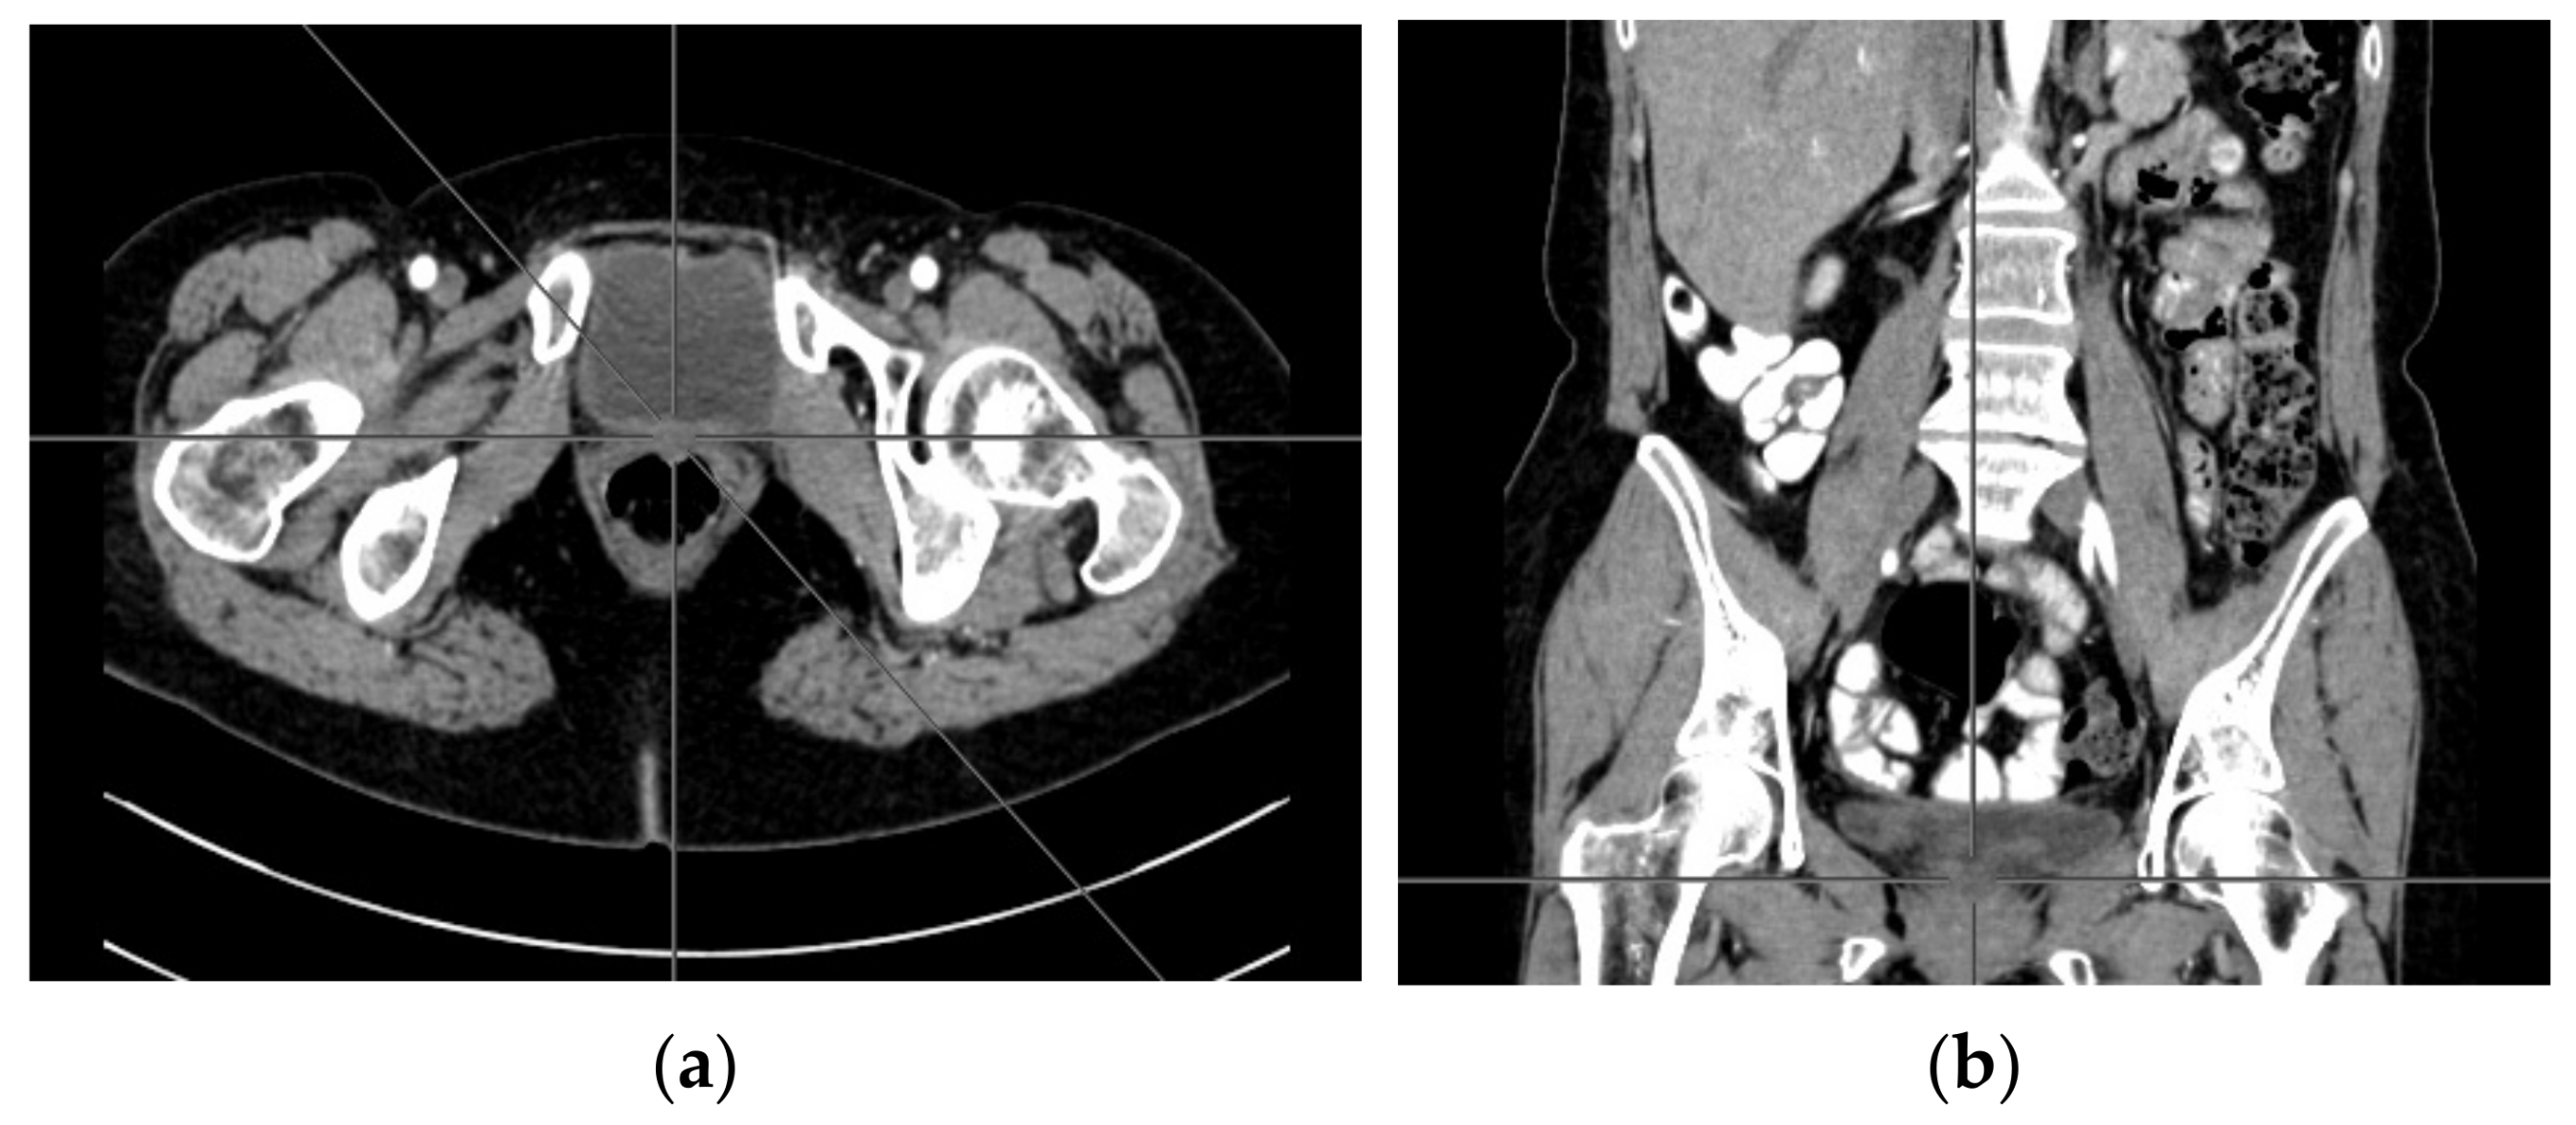

A computer tomography of the abdomen and pelvis was also performed every 3 months for the possible detection of ovarian cancer recurrence. No CT changes suggestive of recurrence were observed in the patient during the treatment. There are illustrates scans on the same section from CT performed at the beginning of PARP inhibitor treatment (Figure 2) and before 48 cycle of olaparib chemotherapy (Figure 3).

Figure 3. (ad) CT scans performed before 48 cycle of olaparib treatment.